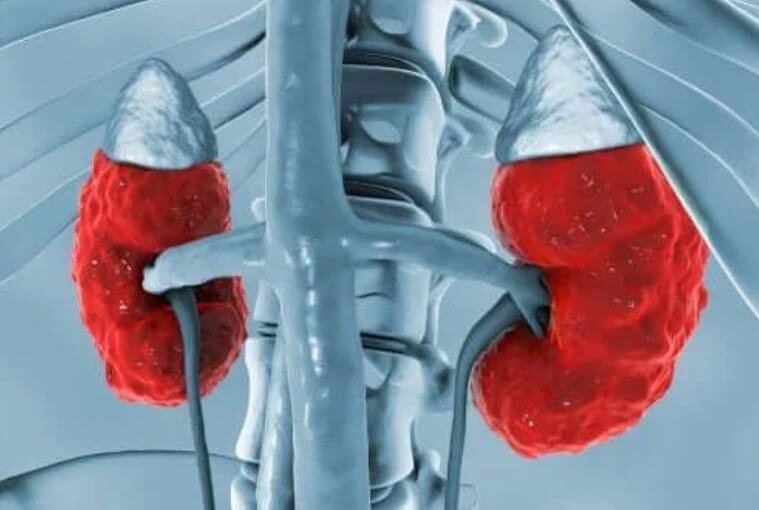

Στα νεφρά

Η δράση της στα νεφρά βελτιώνει μια σειρά διεργασιών που συγκεντρώνουν τα ούρα. Με την προώθηση αυτής της συγκέντρωσης, η αγγειοπιεσίνη παράγει την καθαρή επαναπορρόφηση του ελεύθερου νερού στο εξωκυτταρικό υγρό.

Η αγγειοπιεσίνη δρα στα νεφρά προκαλώντας τρία κύρια αποτελέσματα:

- Αυξάνει τη διαπερατότητα του νερού των αρχικών σωληναρίων συλλογής. Επιπλέον, αυξάνει εκείνο του εξωτερικού και εσωτερικού μυελικού καναλιού στα νεφρά. Έτσι, το νερό απορροφάται και υπάρχει μια απέκκριση πιο συμπυκνωμένων ούρων.

- Επίσης, αυξάνει τη διαπερατότητα του εσωτερικού μυελικού τμήματος του αγωγού συλλογής στο ουρικό οξύ.

- Τέλος, υπάρχει αυξημένη απορρόφηση νατρίου μέσω του ανερχόμενου άκρου του βρόχου του Henle.